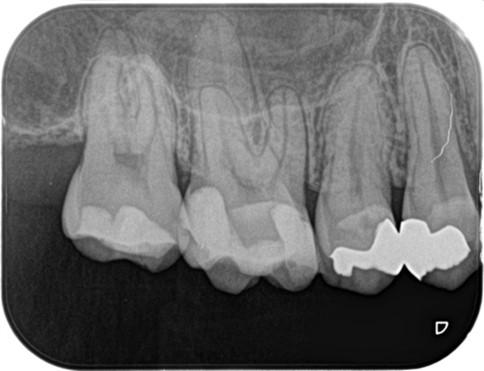

_術前のレントゲン画像|目白マリア歯科.jpg)

_術前のレントゲン画像、虫歯処置の箇所マーク|目白マリア歯科.jpg)